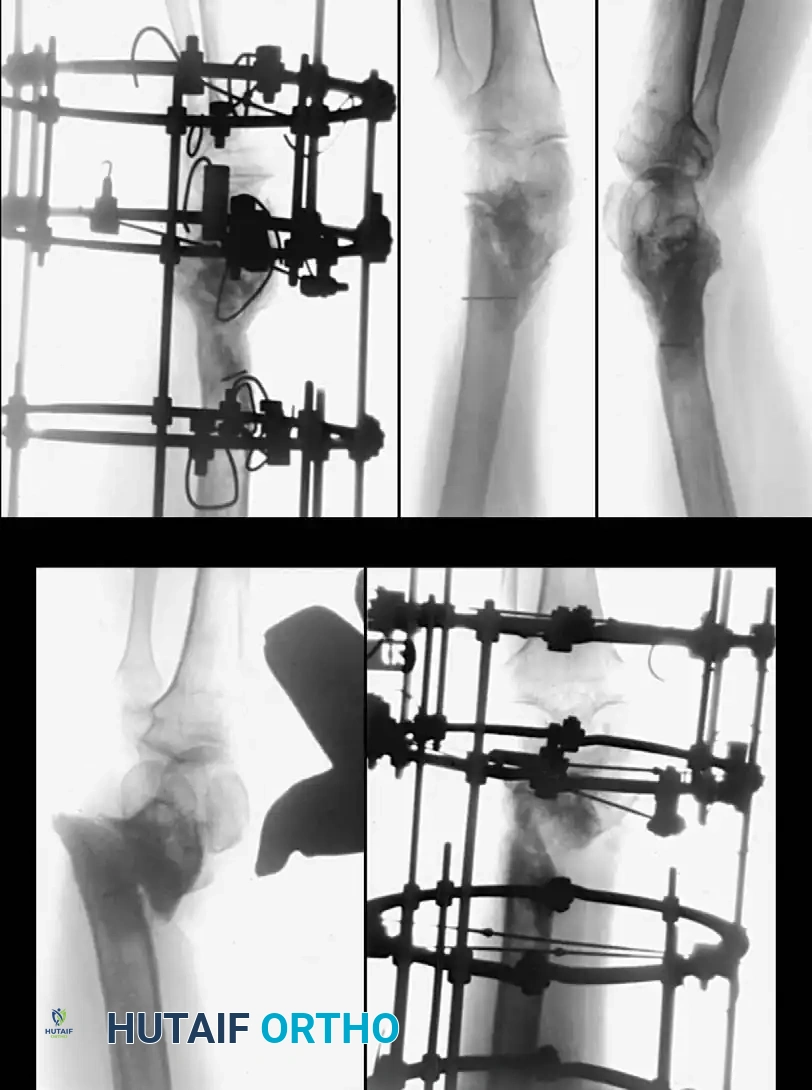

The surgical technique selected depends heavily on whether the nonunion is hypervascular (hypertrophic) or avascular (atrophic), and whether the alignment of the fragments is satisfactory.

- Hypervascular Nonunions: The bone ends possess excellent biological capacity to unite but lack mechanical stability. In these cases, rigid internal fixation with a compression plate, an intramedullary nail, or a circular external fixator is usually all that is necessary. Supplemental bone grafting is rarely required.

- Avascular Nonunions: The bone ends are sclerotic, necrotic, and lack osteogenic potential. Rigid internal fixation must be supplemented by aggressive decortication of the sclerotic bone ends (shingling) and the application of autogenous bone graft. Weber and Brunner, Müller and Thomas, and Christensen have found these combined methods highly successful.

Partial Fibulectomy and Weight Bearing

When the fibula and the tibia are fractured simultaneously, the fibula almost always heals first due to its robust muscular envelope. Once healed, the intact fibula acts as a load-sharing strut that decreases axial loading across the healing tibia. Furthermore, an intact fibula may physically prevent the close apposition of tibial fragments.

Partial fibulectomy removes this strut, allowing closer apposition of the tibial fragments and restoring full axial loading to the tibia, which stimulates osteogenesis according to Wolff's Law.

DeLee, Heckman, and Lewis reported healing in 77% of 51 tibial nonunions after partial fibulectomy. Failures were strongly associated with patient noncompliance (failure to bear weight postoperatively), the presence of a true synovial pseudarthrosis, or previous prolonged external fixation.

Surgical Principles of Fibulectomy:

The full-thickness segment removed from the fibula must be approximately 2.5 cm long. Removal of a smaller segment may allow the fibula to heal before the tibia unites, recreating the strut effect. Following resection, the tibia must be carefully aligned by closed manipulation to prevent a varus deformity. A straight long-leg walking cast is applied for 6 weeks, and aggressive full weight-bearing is encouraged.